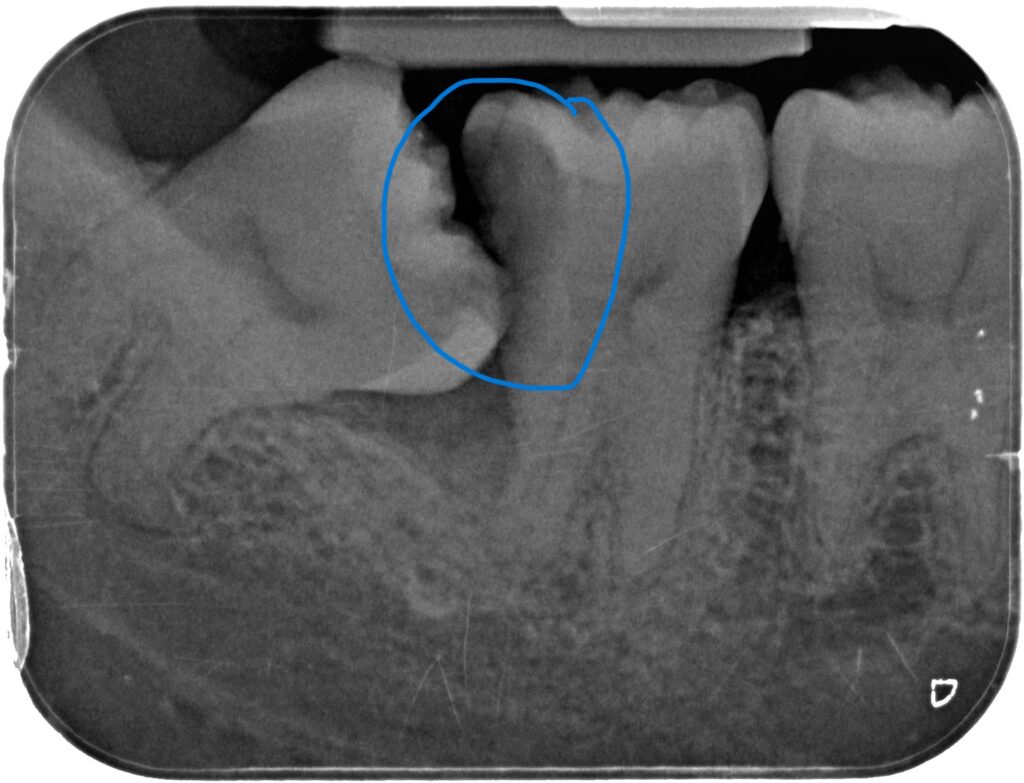

2) Tooth decay

When the impacted tooth hits the neighboring molar tooth, food always get stuck at the region and not easily cleansable. There will be a high risk of developing tooth decay on the wisdom tooth itself and the adjacent molar tooth.

The tooth decay on the adjacent molar are usually formed at the neck region of the tooth, which is hard to detect without X-rays and often very difficult to restore and have poor prognosis. If the adjacent molar is badly decayed, it might require removal together with the wisdom teeth in malay also. Therefore our dentists may suggest to remove the unfavorably positioned wisdom tooth before this happens.